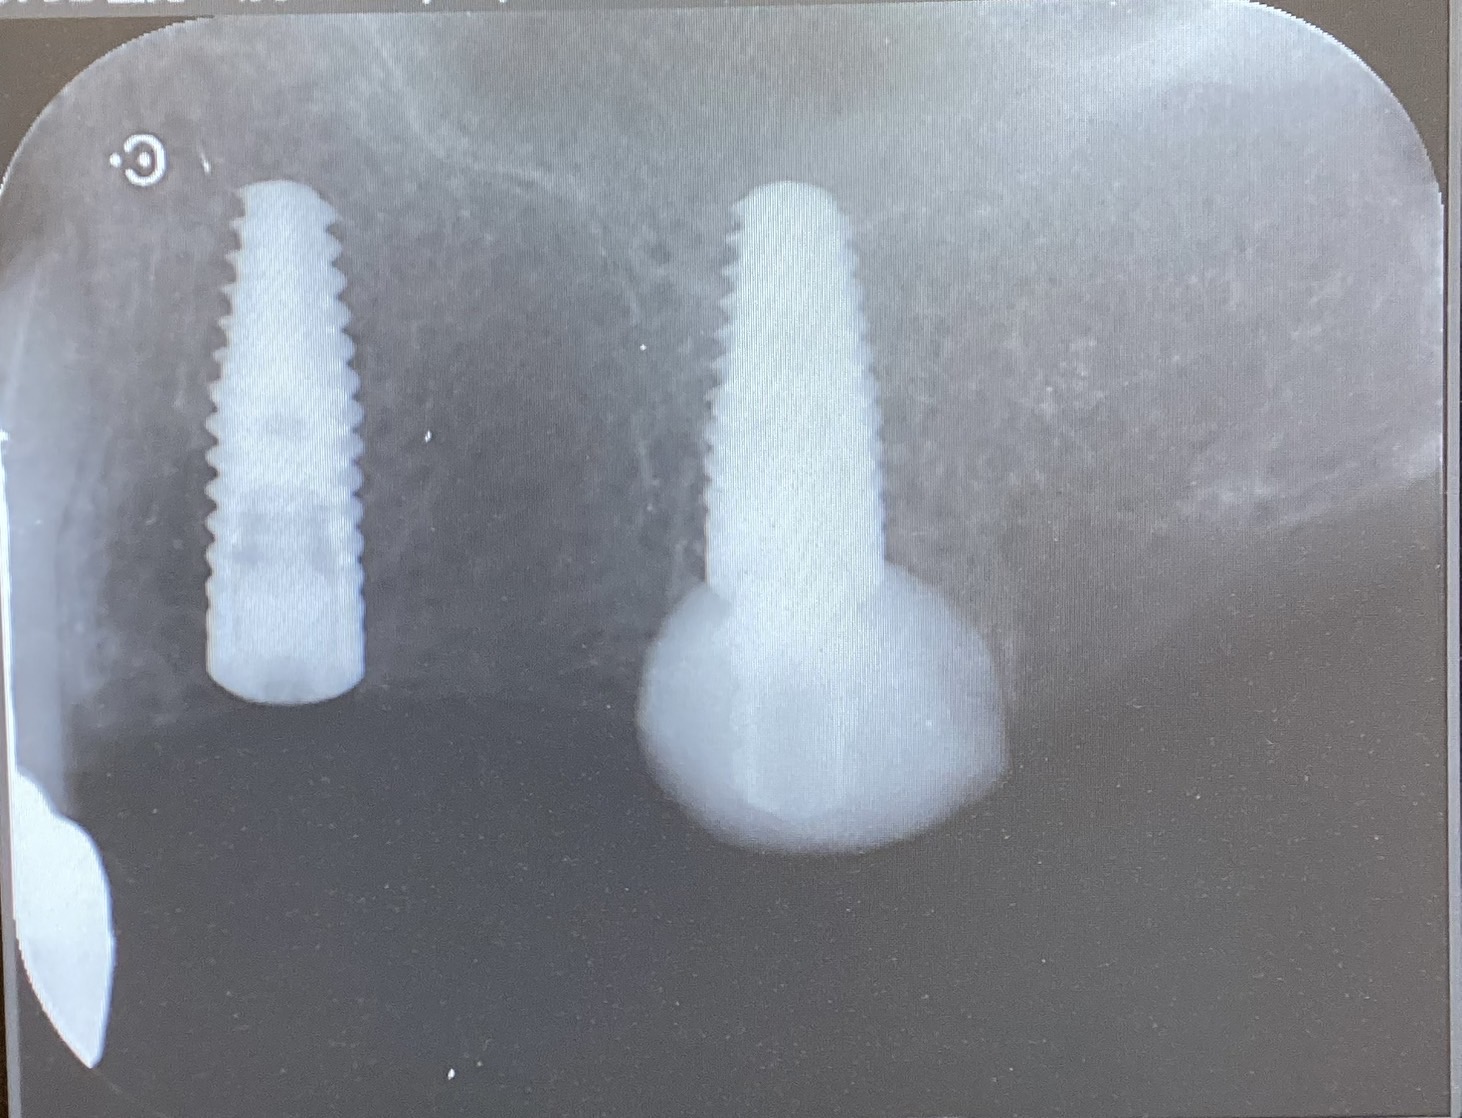

After

抜歯当日にインプラントを埋入する治療です。

抜歯即時埋入は、抜歯当日にインプラントを埋入するため、治療期間を3ヶ月程度短縮することが出来ます。

CT撮影、診断、インプラント埋入、2次オペ、上部構造(被せ物) 全て合わせて30万円(税込)

サージカルガイト 6万円(税込)

抜歯即時埋入 5万円(税込)